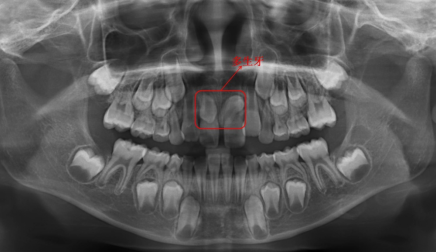

多生牙

多生牙通常是指额外的牙齿,多生牙主要是由于遗传因素或者是牙胚先天发育异常所导致的,如果出现多生牙的情况,容易导致牙齿拥挤,而且参差不齐的不良症状,在吃饭的时候容易出现食物嵌塞的症状,并且还会影响到口腔内的美观,因此如果出现多生牙的情况,要在牙齿已经萌出的情况下拔除,此时拔除牙齿创伤不是很大,而且恢复的也比较快,但是在拔多生牙时要排除是正常恒牙。

多生牙位置是比较深的,长期不处理是会影响周围的组织的,因此需要找到合适的时机拔除。